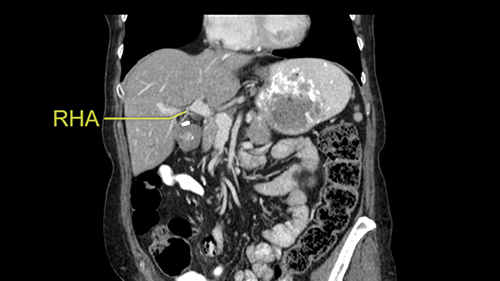

The procedure-specific slowing down moments from a technical point of view for a right hemihepatectomy include a careful evaluation of the inflow structures including the right hepatic artery, the right portal vein, as well to make sure that I have identified and preserved the left hepatic artery and the left portal vein at all times, and minimize any injury or dissection of the common bile duct. Also, I am careful when I mobilize the right liver, not to tear the right triangular ligament and cause bleeding of the liver as I mobilize it off the retroperitoneum and the bare area. In addition, the last procedure-specific slowing down moment is to carefully identify the right hepatic vein and ensure that I encircle it safely without damaging the IVC or the middle and left hepatic vein structures at all times.

So I would then focus on the hepatic outflow because that’s the way we do the operation is by mobilizing the liver. So the vena cava looks quite normal. The right hepatic vein looks quite normal. There are no large additional outflow veins from the right lobe which would generate slowing down moments. The hepatic artery is unremarkable and is not usually an issue we can define the anatomy quite clearly at surgery.

![[RHA]](jpg/preop_sg_moment3.jpg)

If I need to control the right inflow pedicle, I’ll take the gallbladder dissection down to nicely show the right hepatic ducts so I know where the right hepatic duct is. Look behind the right hepatic duct, always you have the right hepatic artery there so right hepatic artery can be divided between right angle forceps, divided and ligated. Once that’s done, the only structure behind you is the right portal vein. If you use an eyelid retractor or Desmarres forceps just to hold the bile duct up, you see the main portal vein, you’ll probably see some caudate branches, and then you see what I call the ‘hammerhead’ of the portal vein bifurcation. It's a very distinctive, very constant landmark: right portal vein, left portal vein. We can then encircle the right portal vein and quite often it’s sufficient in right hepatectomy for this sort of situation to ligate it in continuity. It definitely doesn't need a big vascular stapler in there because what you don’t want to do when you’re closing the right portal vein is to compromise the left. So I will encircle the right portal vein, I’ll move the forceps just a little bit away from the confluence, be sure that I’m absolutely not compromising the left portal vein and tie it with an absorbable suture. I’m going to staple it within the liver. Now then we’re at a situation where we can come to do transection. You can do transection in one of very many different methods. All of which are probably equal.